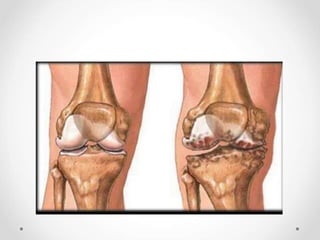

Foto Rontgen

Penyempitan celah sendi yang seringkali

asimetris

Osteofit pada pinggir sendi

Peningkatan densitas (sclerosis) tulang

subkondral

Kista tulang

Perubahan struktur anatomi sendi

Pencitraan radiologis sinar-x osteoarthritis pada lutut

Gambaran radiologis anteroposterior lutut menunjukkan penyempitan

ruang sendi, sklerosis, dan pembentukan osteofit (panah)

Sumber : Jacobson, JA, et al. 2008. Radiographic Evaluation of Arthritis : Degenerative Joint Disease and Variation. Radiology. 248(3) : 737-747.

Adanya pembentukan osteofit dan

penyempitan celah sendi pada

sendi tungkai

Gambaran sendi tungkai normal